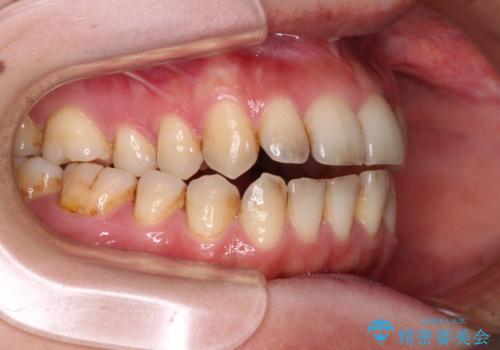

- 上下前歯の隙間を気にして来院された患者様です。

下顎前歯が1本欠損しており、上下小臼歯はクロスバイトとなり、上下前歯の接触もないという不正咬合の状態でした。

クロスバイトはワイヤー矯正が得意とするところであり、上下前歯の非接触や開咬はインビザラインの得意とするところであるので、ワイヤー装置により事前にクロスバイトを改善し、その後にインビザラインにて仕上げていくこととしました。